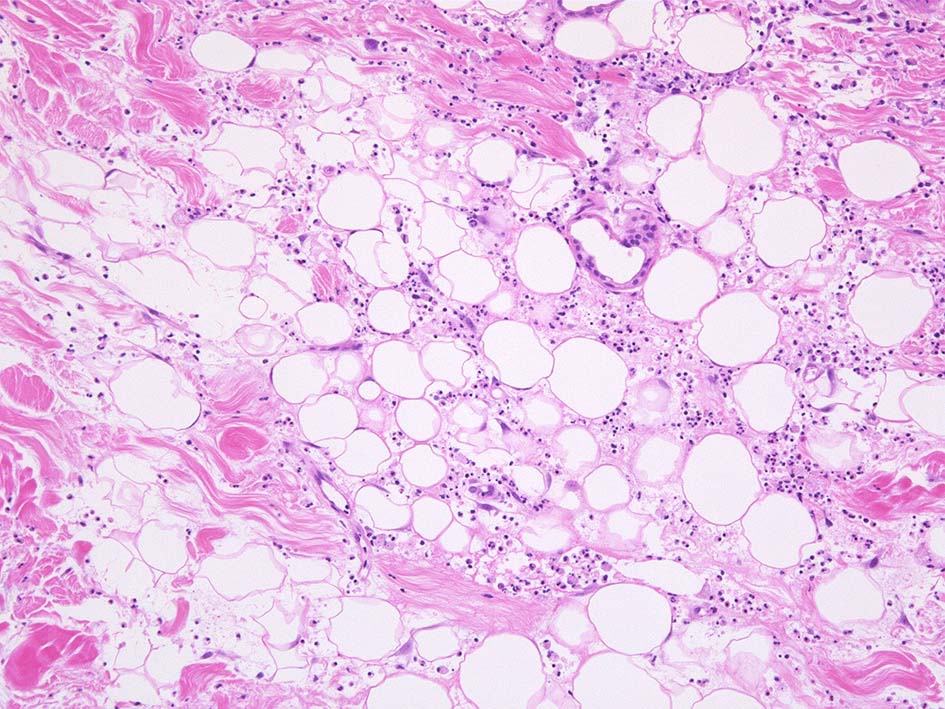

HE x40. 表皮下水疱あり. 真皮上層は浮腫状. 真皮から皮下組織にかけて, 多数の好中球が浸潤している. リンパ球, 好酸球が混在, 核破砕物を貪食するマクロファージが増加. 膠原線維にはところどころ変性が見られる.

皮下脂肪織炎病変には局所的なhemophagocytosisが認められる. 血管にはfibrinoid necrosisは見られない。